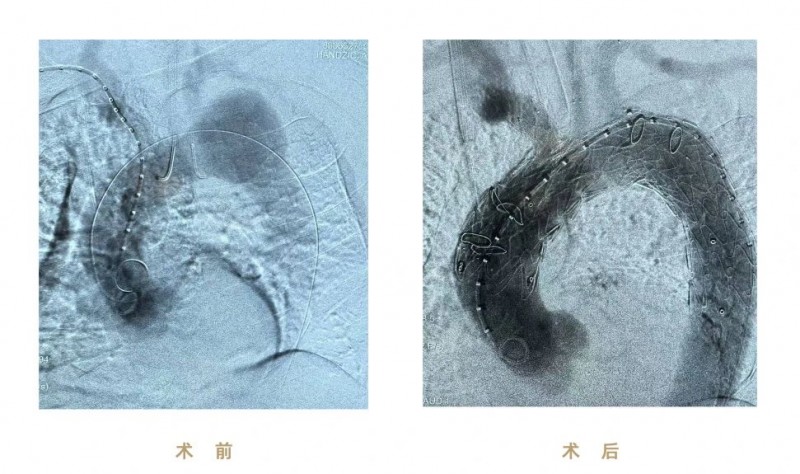

(图:术前、术后影像)

本次手术使用先健CS一体式弓部三分支重建系统进行腔内修复,逐次完成通路建立、CS主体支架植入及精准释放、弓上三分支(无名动脉、左颈总动脉、左锁骨下动脉)依次超选及分支支架植入,全程造影显示支架形态良好、无移位及内漏、三分支血流通畅,达到理想的隔绝与血供重建效果。